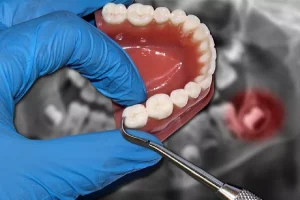

In medicine, wisdom teeth are also called third molars. They are the eighth teeth from front to back. Wisdom teeth are the last permanent

There are 32 teeth in the human permanent dentition, of which the last four third molars are located at the back of the upper,